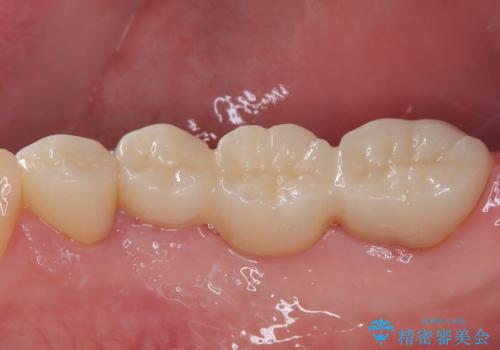

- 左下の4番目のセラミックの詰め物(セラミックインレー)が欠けたとのことで来院された患者様です。以前にセラミックの詰め物の治療を行い、噛み合わせが強く割れてしまっていました。今回はセラミックの詰め物のやり替えだとまた欠けてしまう可能性があるのでフルジルコニアクラウンでの治療を行うことにしました。拡大鏡視野下でセラミックの詰め物、虫歯を除去しフルジルコニアクラウンに適した形に整えました。

歯と歯茎の間に圧排糸と呼ばれる糸を入れてシリコーン印象を行いました。

見た目、機能面ともに満足していただけました。

噛み合わせが強い方なので今後はセラミックが割れないようにナイトガードを使っていただきながら、定期的にクリーニングで通ってもらう予定です。